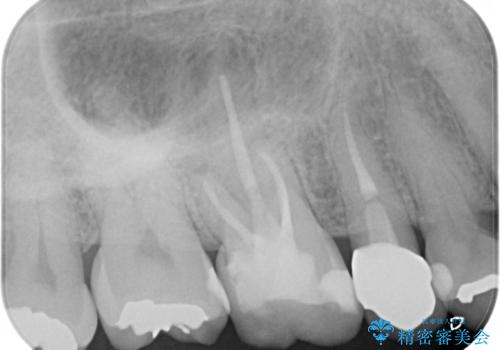

- 定期検診にて、奥歯の頬側歯肉にサイナストラクトが発見された患者様です。

根管治療から歯冠修復まで行っております。

サイナストラクト(瘻孔)から原因歯を特定し治療を行っております。根管治療を行った歯牙は破折リスクが高くなるため被せものによる治療を提案しております。